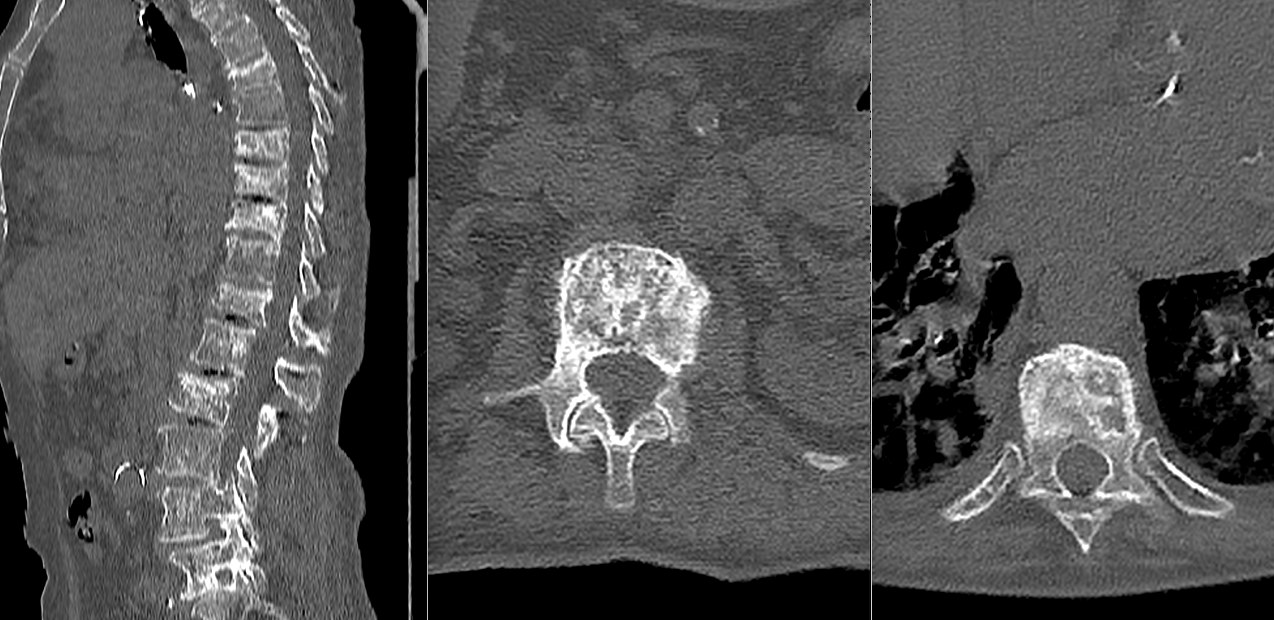

Diagnosticul tumorilor spinale osoase se bazează pe imagistică de înaltă performanță. Rezonanța magnetică este investigația principală, deoarece oferă informații detaliate despre os, măduvă și nervi. Tomografia computerizată este utilă pentru evaluarea distrugerii osoase.

În multe cazuri, este necesară o biopsie pentru a stabili cu certitudine natura tumorii. Acest pas este crucial înainte de inițierea tratamentului.